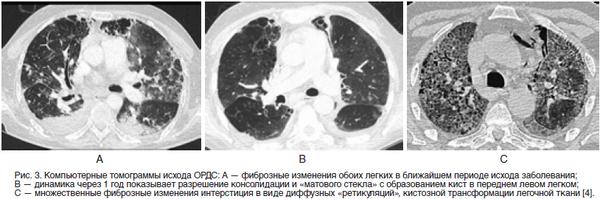

ы матового стекла